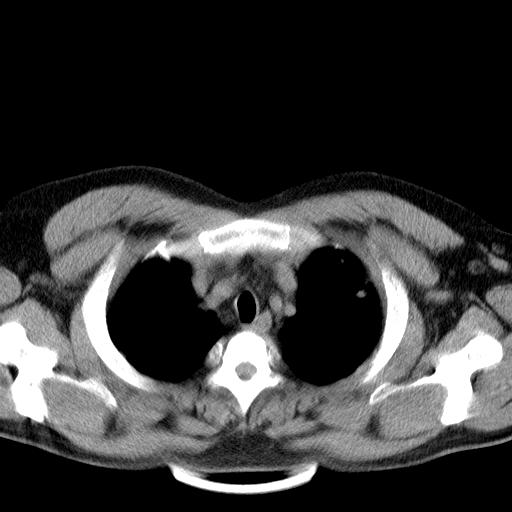

增强扫描。

补充一下各种检查结果,病人无痰,胸闷,ppd及结核抗体阴性,wbc7.5x10的9次方,血沉22mm/h,crp及抗链o阳性。

哦cea8

经一周抗炎抗病毒治疗复查胸片示病变大部吸收,基本恢复正常,未做气管镜检查,考虑为炎性变或霉菌感染。